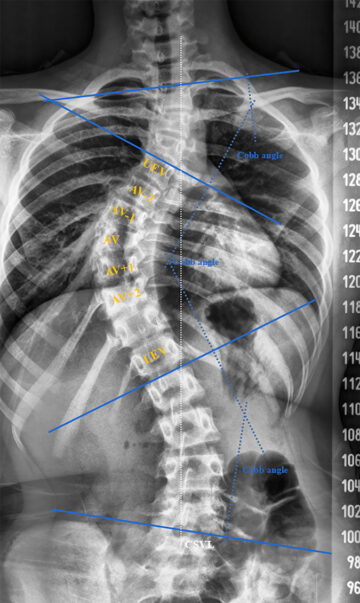

تشوهات الصدر عند مرضى اعوجاج العمود الفقري: الأسباب والعلاج يُعد اعوجاج العمود الفقري المراهقي مجهول السبب (Adolescent Idiopathic Scoliosis – AIS) من الحالات الشائعة التي تحتاج إلى تقييم دقيق للانحناء والالتواء، لذلك يُعتبر الالتواء

تأثير اعوجاج العمود الفقري على شكل الفقرات | علامات يجب أن تعرفها مبكرً…

تأثير اعوجاج العمود الفقري على شكل الفقرات | علامات يجب أن تعرفها مبكرً يعاني بعض المراهقين من اعوجاج العمود الفقري المعروف بالجنف، وهو انحناء غير طبيعي للظهر يمكن أن يغير شكل الجسم ويزداد مع

كيف يؤثر اعوجاج العمود الفقري على القفص الصدري و الأضلاع عند المراهقين؟…

كيف يؤثر اعوجاج العمود الفقري على القفص الصدري و الأضلاع عند المراهقين؟ مقدمة اعوجاج العمود الفقري عند المراهقين، المعروف بالجنف، ليس مجرد انحناء جانبي للظهر، بل يترافق أحيانًا مع تغير في شكل القفص الصدري.